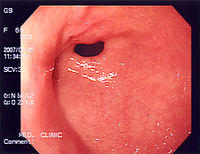

A series of radiographs can be used to examine the stomach for various disorders. This will often include the use of a barium swallow. Another method of examination of the stomach, is the use of an endoscope. A gastric emptying scan is considered the gold standard to assess gastric emptying rate.[43]

Endoscopic image of human fundic gland polyposis.